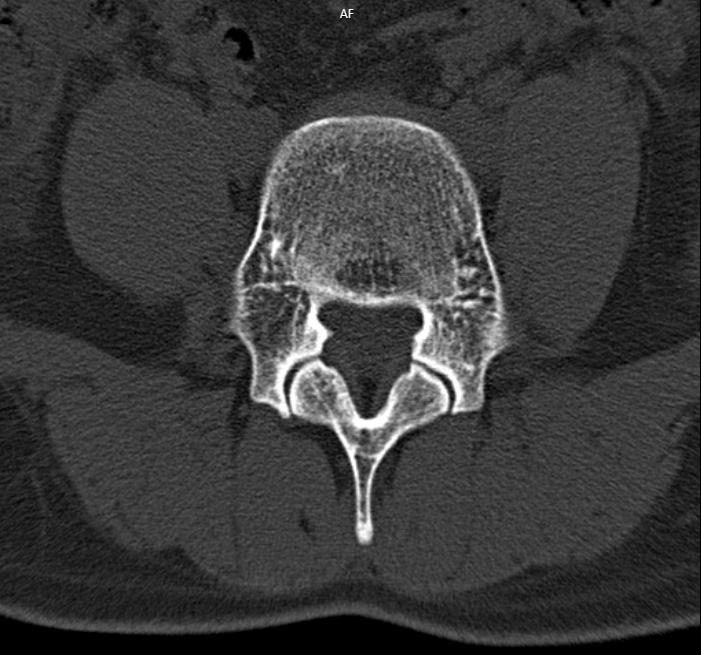

4 9 岁女性患者因工作原因患上了腰突症,检查报告提示腰椎生理曲度变直, 腰 5- 骶1 椎间盘局限性向后突出,硬膜囊受压,骨性椎管无狭窄,有骨质增生。查看舌苔,舌淡红,苔薄白,属于脾虚,气血不足。